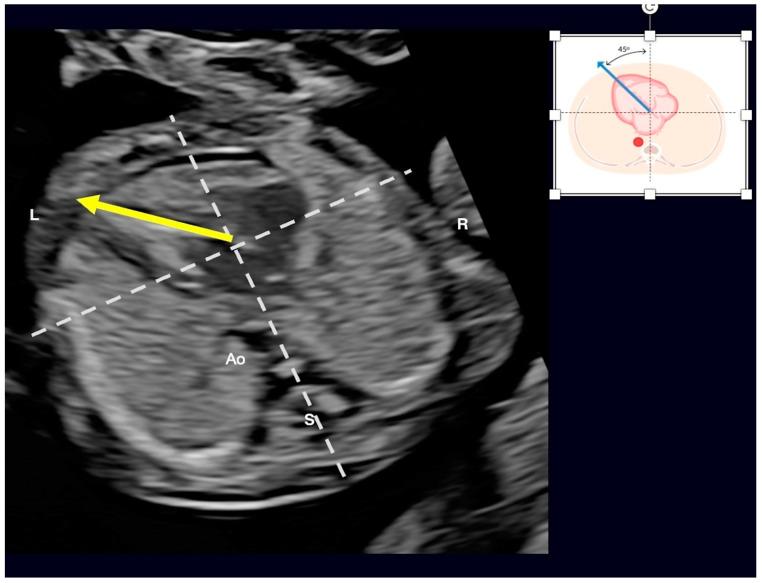

Congenital heart defects (CHDs) are the most common congenital defect, occurring in approximately 1 in 100 live births and being a leading cause of perinatal morbidity and mortality. Of note, approximately 25% of these defects are classified as critical, requiring immediate postnatal care by pediatric cardiology and neonatal cardiac surgery teams. Consequently, early and accurate diagnosis of CHD is key to proper prenatal and postnatal monitoring in a tertiary care setting. In this scenario, fetal echocardiography is considered the gold standard imaging ultrasound method for the diagnosis of CHD. However, the availability of this examination in clinical practice remains limited due to the need for a qualified specialist in pediatric cardiology. Moreover, in light of the relatively low prevalence of CHD among at-risk populations (approximately 10%), ultrasound cardiac screening for potential cardiac anomalies during routine second-trimester obstetric ultrasound scans represents a pivotal aspect of diagnosing CHD. In order to maximize the accuracy of CHD diagnoses, the views of the ventricular outflow tract and the superior mediastinum were added to the four-chamber view of the fetal heart for routine ultrasound screening according to international guidelines. In this context, four-dimensional spatio-temporal image correlation software (STIC) was developed in the early 2000s. Some of the advantages of STIC in fetal cardiac evaluation include the enrichment of anatomical details of fetal cardiac images in the absence of the pregnant woman and the ability to send volumes for analysis by an expert in fetal cardiology by an internet link. Sequentially, new technologies have been developed, such as fetal intelligent navigation echocardiography (FINE), also known as "5D heart", in which the nine fetal cardiac views recommended during a fetal echocardiogram are automatically generated from the acquisition of a cardiac volume. Furthermore, artificial intelligence (AI) has recently emerged as a promising technological innovation, offering the potential to warn of possible cardiac anomalies and thus increase the ability of non-cardiology specialists to diagnose CHD. In the early 2010s, the advent of 3D reconstruction software combined with high-definition printers enabled the virtual and 3D physical reconstruction of the fetal heart. The 3D physical models may improve parental counseling of fetal CHD, maternal-fetal interaction in cases of blind pregnant women, and interactive discussions among multidisciplinary health teams. In addition, the 3D physical and virtual models can be an useful tool for teaching cardiovascular anatomy and to optimize surgical planning, enabling simulation rooms for surgical procedures. Therefore, in this review, the authors discuss advanced image technologies that may optimize prenatal diagnoses of CHDs.

先天性心脏病(CHD)是最常见的先天性缺陷,约每100例活产中就有1例发生,是围产期发病和死亡的主要原因。值得注意的是,这些缺陷中约25%被归类为重症,需要儿科心脏病学和新生儿心脏外科团队在出生后立即进行护理。因此,在三级医疗环境中,早期准确诊断CHD是进行适当产前和产后监测的关键。在这种情况下,胎儿超声心动图被认为是诊断CHD的金标准成像超声方法。然而,由于需要合格的儿科心脏病学专家,这种检查在临床实践中的可用性仍然有限。此外,鉴于高危人群中CHD的患病率相对较低(约10%),在常规孕中期产科超声扫描期间对潜在心脏异常进行超声心脏筛查是诊断CHD的一个关键方面。为了最大限度地提高CHD诊断的准确性,根据国际指南,在胎儿心脏的四腔心视图中增加了心室流出道和上纵隔的视图用于常规超声筛查。在这种背景下,四维时空图像相关软件(STIC)于21世纪初开发。STIC在胎儿心脏评估中的一些优点包括在孕妇不在场的情况下丰富胎儿心脏图像的解剖细节,以及能够通过互联网链接将容积发送给胎儿心脏病学专家进行分析。随后,开发了新技术,如胎儿智能导航超声心动图(FINE),也称为“5D心脏”,其中在胎儿超声心动图检查期间推荐的九个胎儿心脏视图是从心脏容积采集中自动生成的。此外,人工智能(AI)最近作为一种有前途的技术创新出现,有可能警告可能的心脏异常,从而提高非心脏病学专家诊断CHD的能力。在21世纪10年代初,3D重建软件与高清打印机的出现使得胎儿心脏的虚拟和3D实体重建成为可能。3D实体模型可以改善对胎儿CHD的家长咨询、盲孕孕妇的母婴互动以及多学科医疗团队之间的互动讨论。此外,3D实体和虚拟模型可以成为教授心血管解剖学和优化手术规划的有用工具,为手术操作提供模拟室。因此,在本综述中,作者讨论了可能优化CHD产前诊断的先进图像技术。